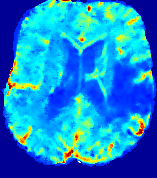

LesionRefer to captionRefer to captionRefer to captionRefer to captionRefer to captionRefer to caption𝐕rgbsubscript𝐕𝑟𝑔𝑏{\bf{V}}_{rgb}Refer to captionRefer to captionRefer to captionRefer to captionRefer to captionRefer to caption𝐕2subscriptnorm𝐕2{\|\bf{V}}\|_{2}Refer to captionRefer to captionRefer to captionRefer to captionRefer to captionRefer to captionRefer to caption3.53.53.52.82.82.82.12.12.11.41.41.40.70.70.70.00.00.0(mm/s)𝑚𝑚𝑠(mm/s)D𝐷DRefer to captionRefer to captionRefer to captionRefer to captionRefer to captionRefer to captionRefer to caption0.0200.0200.0200.0160.0160.0160.0120.0120.0120.0080.0080.0080.0040.0040.0040.0000.0000.000(mm2/s)𝑚superscript𝑚2𝑠(mm^{2}/s)Slice #1Slice #2Slice #3Slice #4Slice #5Slice #6

Figure 4: PIANO feature maps for another patient in the ISLES 2017 training set, where the lesion is located in the right hemisphere. Top row: segmented stroke lesion region (white) on different slices. The corresponding slices for the PIANO feature maps are shown in the following rows.

For a better insight into an estimated velocity field 𝐕𝐕{\bf{V}} and diffusion field 𝐃𝐃{\bf{D}}, we compute the following maps: (1) 𝐕rgbsubscript𝐕𝑟𝑔𝑏{\bf{V}}_{rgb}: Color-coded orientation map of 𝐕=(Vx,Vy,Vz)T𝐕superscriptsuperscript𝑉𝑥superscript𝑉𝑦superscript𝑉𝑧𝑇{\bf{V}}=(V^{x},V^{y},V^{z})^{T}, obtained by normalizing 𝐕𝐕{\bf{V}} to unit length and mapping its 3 components to red, green, blue respectively; (2) 𝐕2subscriptnorm𝐕2\|{\bf{V}}\|_{2}: 222 norm of 𝐕𝐕{\bf{V}}; (3) D𝐷D: scalar field in Eq. 5.

Fig. 3 and Fig. 4 show the PIANO feature maps estimated from two ISLES 2017 patients: all are highly consistent with the lesion in both cases. Details of the blood flow trajectories are revealed in 𝐕rgbsubscript𝐕𝑟𝑔𝑏{\bf{V}}_{rgb} by the ridged patterns and the sharp changes of colors in the unaffected (right) hemisphere, while the flat patterns appearing within the lesion provide little directional information about the velocity and indicate low velocity magnitudes. Velocity magnitudes are more directly visualized via 𝐕2subscriptnorm𝐕2\|{\bf{V}}\|_{2}, from which one can easily locate the lesion where 𝐕2subscriptnorm𝐕2\|{\bf{V}}\|_{2} is low. D𝐷D also indicates lower diffusion values in the lesion, though with less contrast potentially due to the fact that it captures the accumulated effect of CA diffusion at the voxel-level.